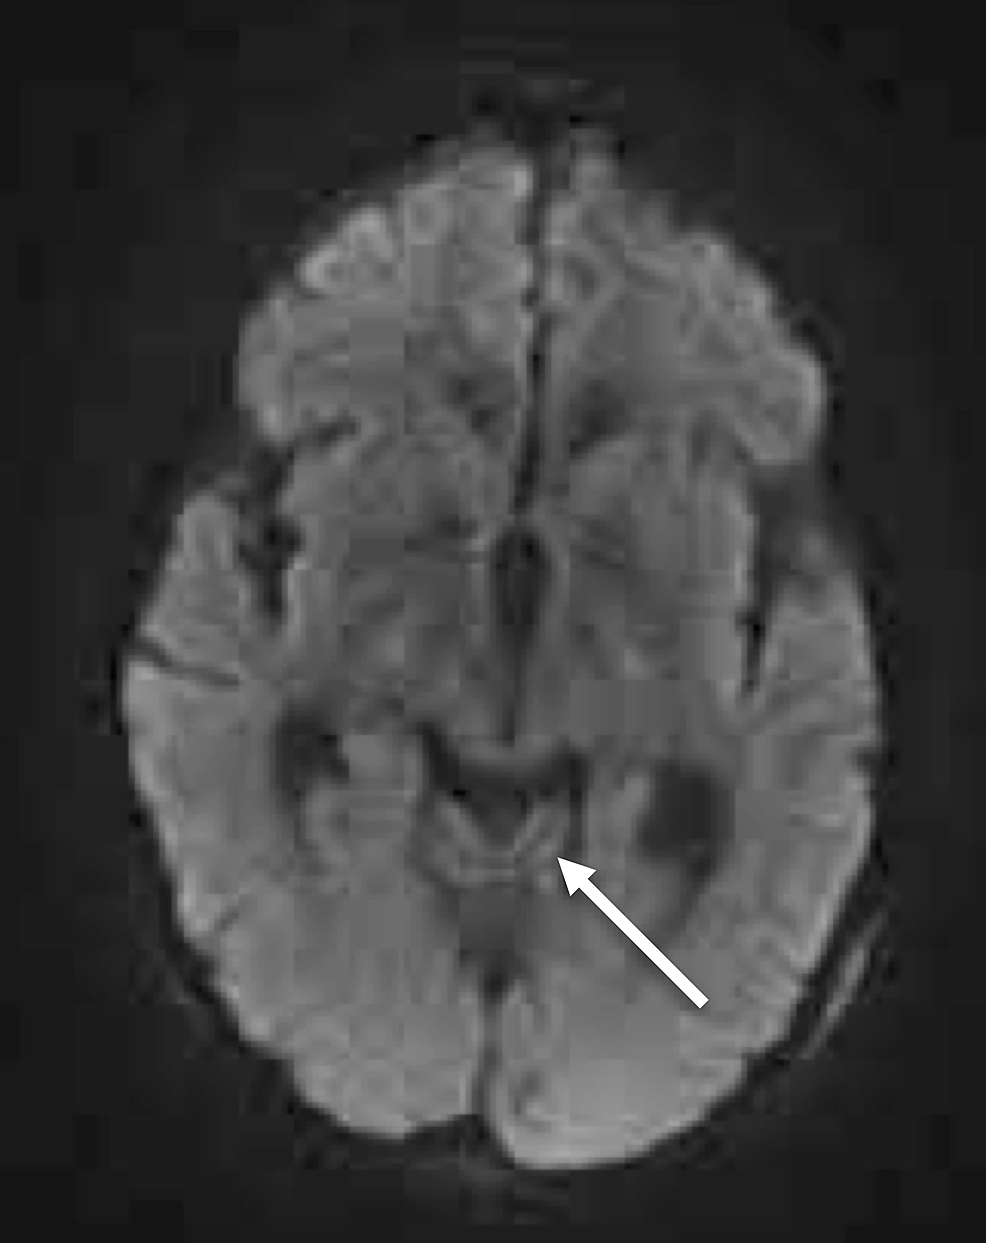

A CT of her brain revealed cerebellar vermian atrophy but was otherwise unremarkable (Figure 1).

MRI of her brain demonstrated cerebellar volume loss, increased FLAIR signal in the cerebellar vermis, normal corpus callosum and normal mammillary bodies (Figures 2-7).

Although not required for a diagnosis of acute WE, “typical” MRI findings include hyperintense FLAIR/T2 signal in the thalami, mammillary bodies, tectal plate, periphery of the third ventricle, and periaqueductal area [3,6]. Approximately 50% of patients with WE exhibit “atypical" MRI findings including FLAIR/T2 hyperintensity in the superior cerebellum, cranial nerve nuclei, red nuclei, dentate nuclei, caudate nuclei, splenium, and cerebral cortex [6]. Historically, these “typical” findings were thought to be more associated with alcoholics while the “atypical” findings were more associated with non-alcoholics. However, recent literature suggests that “typical” and “atypical” findings are less closely linked to alcohol-related and non-alcohol related WE than previously reported, as in our patient with alcohol-related WE displaying only “atypical” MRI features [7]. Differential diagnosis in patients with MRI findings of WE would include arterial/venous infarction (expected to show restricted diffusion), viral encephalitis (expected to have greater areas of increased FLAIR/T2 signal; atrophy would be unusual) and Marchiafava-Bignami Disease (expected to have callosal signal abnormality).